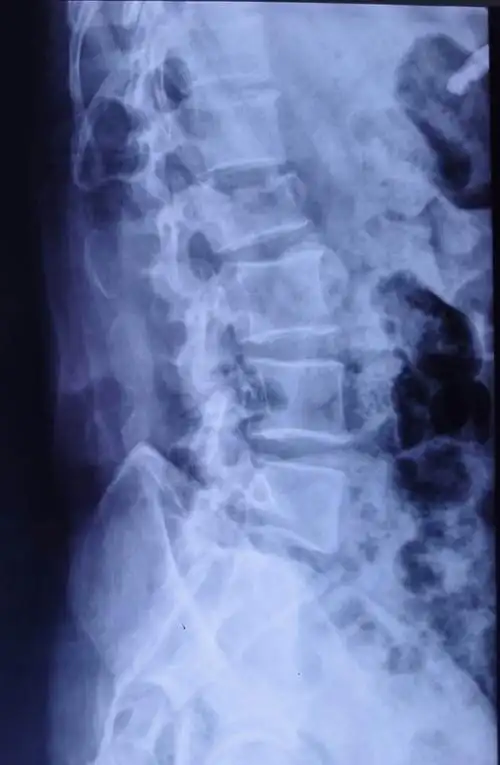

腰2椎体压缩性骨折,闭合复位微创经皮钉棒系统内固定手术治疗.

术前x线平片示腰2椎体明显压缩骨折,压缩约1/2.